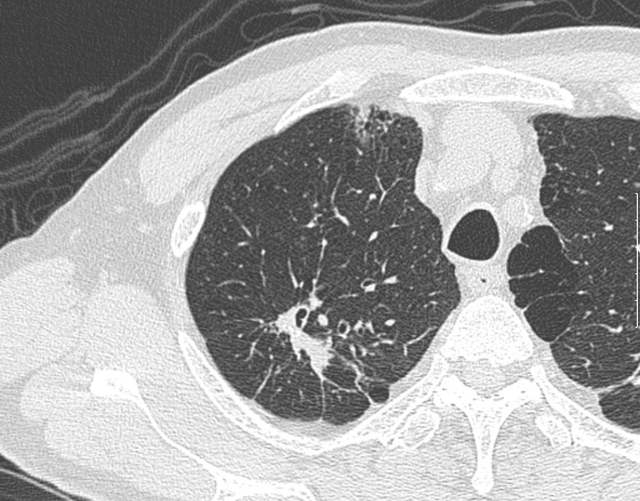

当院では、胸部CT検査時に適宜、高分解能CT画像HRCT(high-resolution CT)を追加処理しています。通常のCTと比べて、明瞭に病変部の性状を把握することができます。

高分解能CT画像HRCT

1mm実効スライスにて高空間周波数アルゴリズムを用いた拡大画像を追加することで、小結節性病変等の検出能を高め、診断能の向上に努めています。